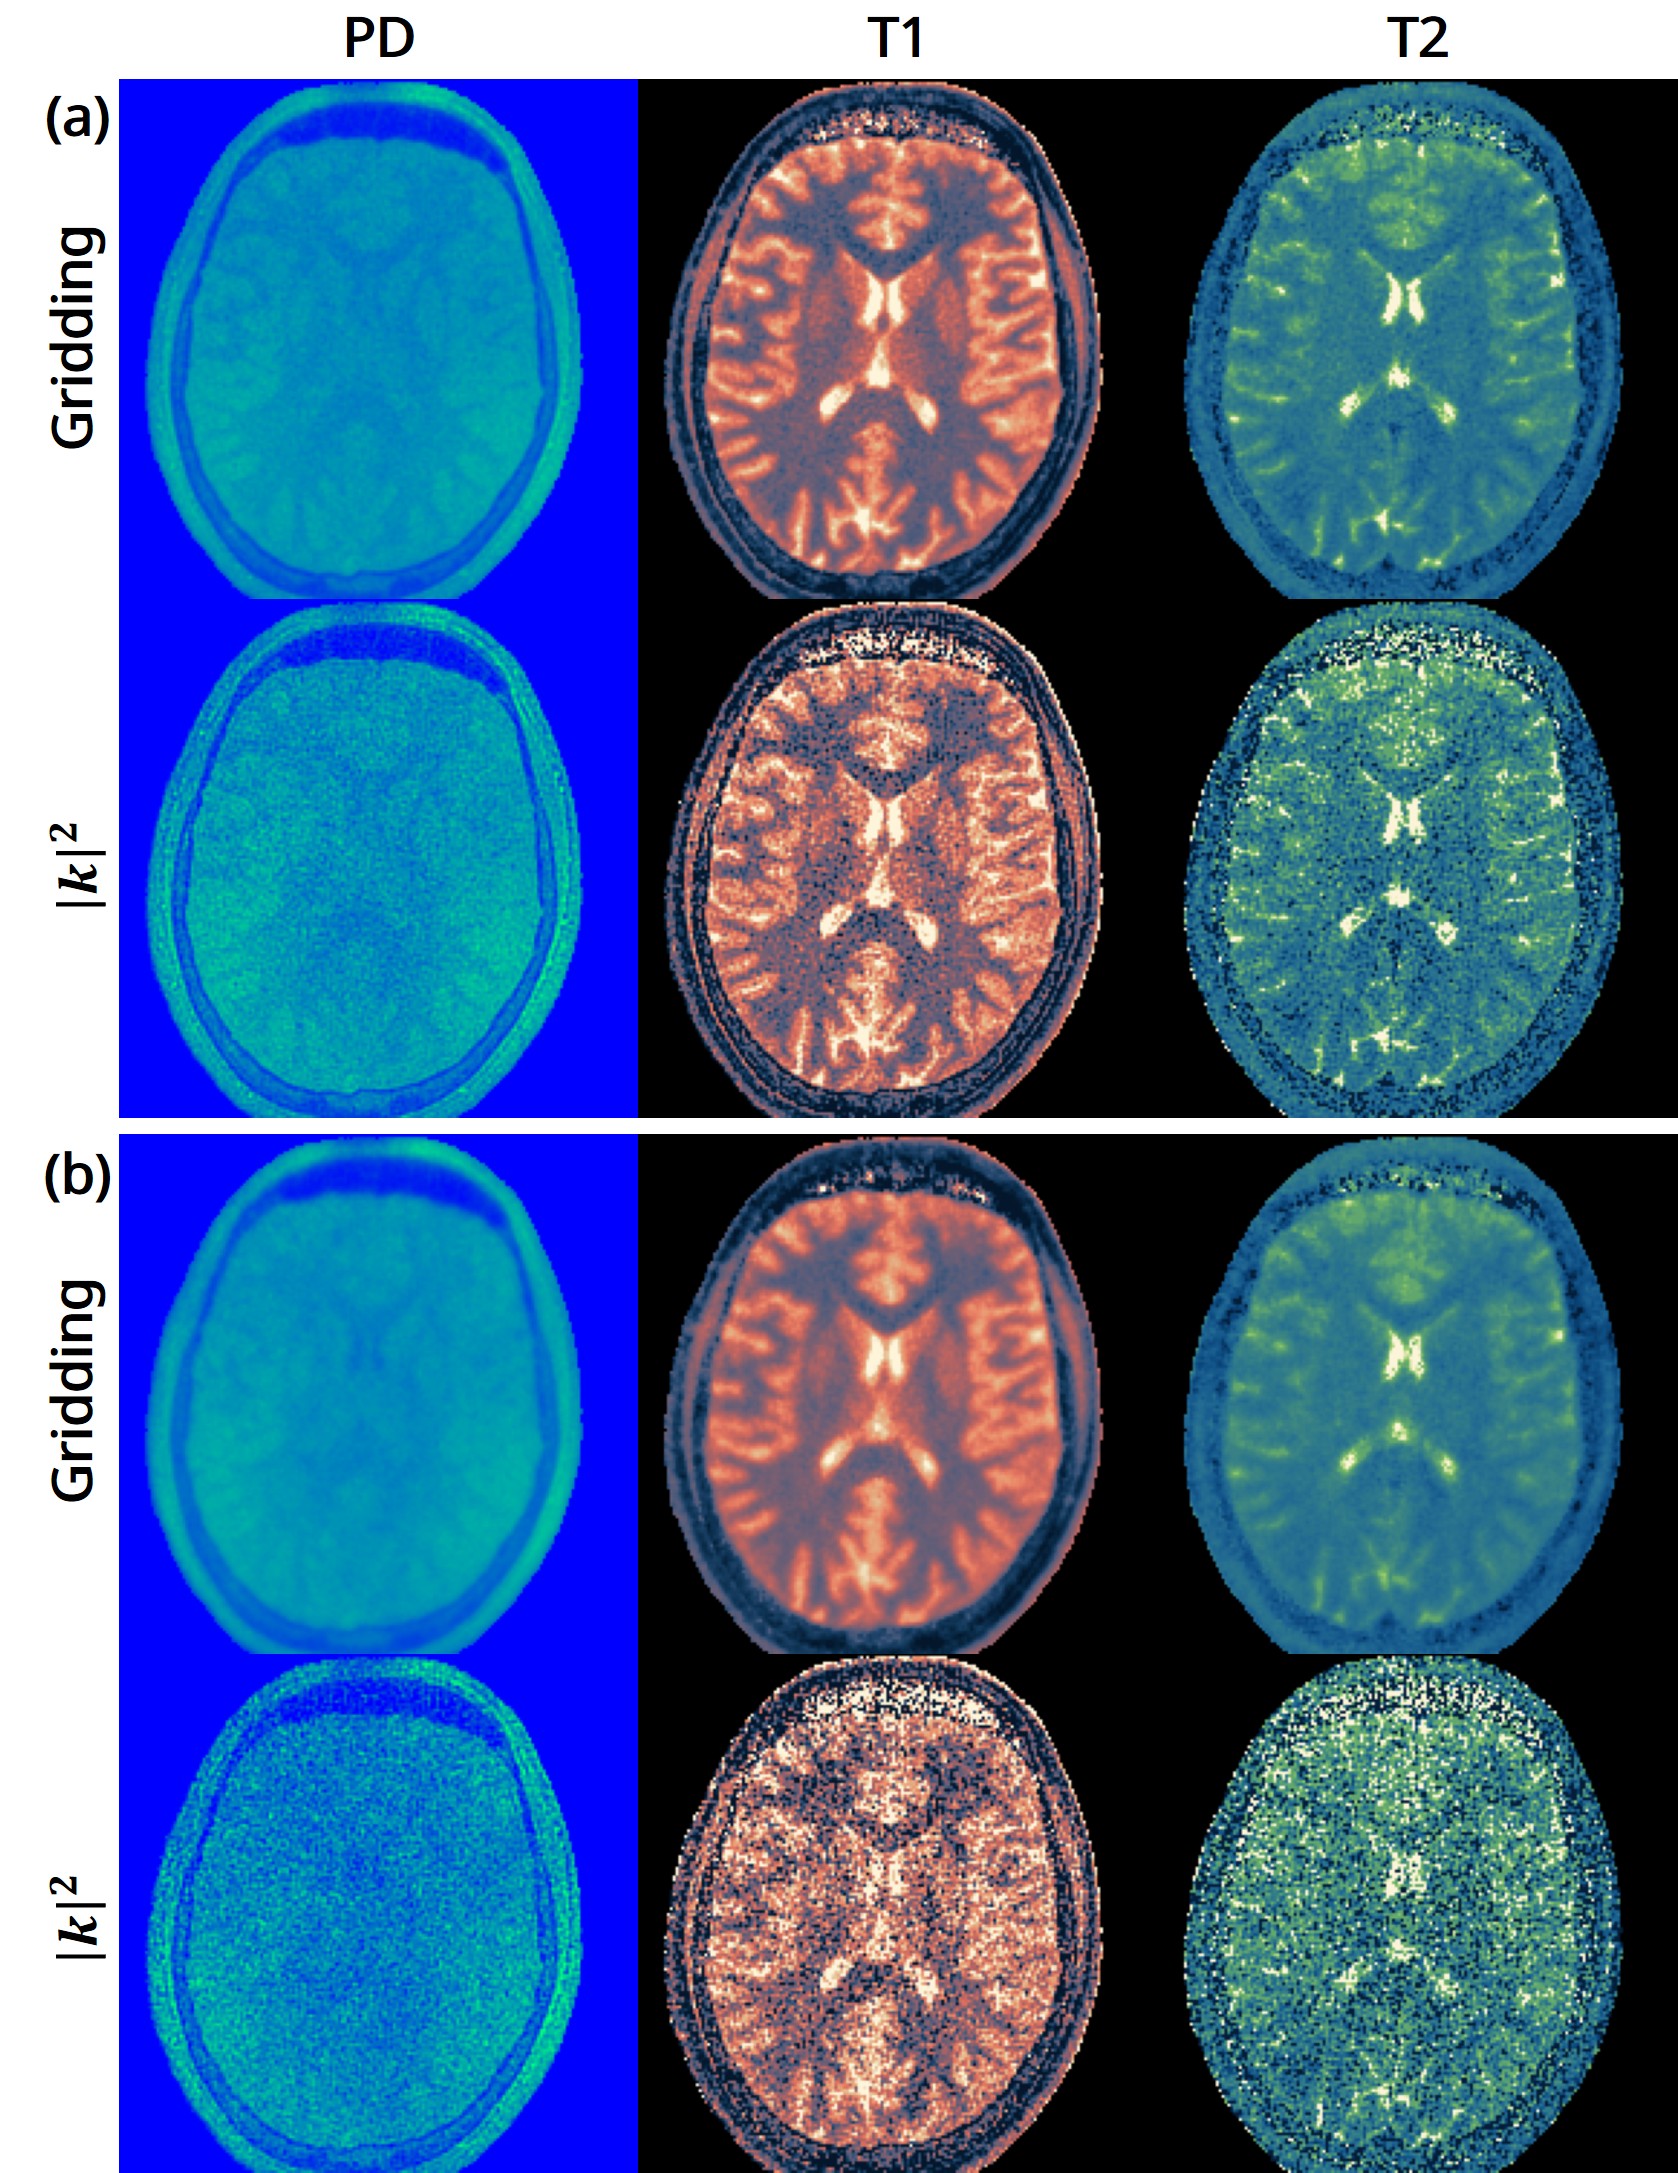

The 3D fast silent multi-parametric mapping sequence with zero echo time (MuPa-ZTE) is a novel quantitative MRI (qMRI) acquisition that enables nearly silent scanning by using a 3D phyllotaxis sampling scheme. MuPa-ZTE improves patient comfort and motion robustness, and generates quantitative maps of T1, T2, and proton density using the acquired weighted image series. In this work, we propose a diffusion model-based qMRI mapping method that leverages both a deep generative model and physics-based data consistency to further improve the mapping performance. Furthermore, our method enables additional acquisition acceleration, allowing high-quality qMRI mapping from a fourfold-accelerated MuPa-ZTE scan (approximately 1 minute). Specifically, we trained a denoising diffusion probabilistic model (DDPM) to map MuPa-ZTE image series to qMRI maps, and we incorporated the MuPa-ZTE forward signal model as an explicit data consistency (DC) constraint during inference. We compared our mapping method against a baseline dictionary matching approach and a purely data-driven diffusion model. The diffusion models were trained entirely on synthetic data generated from digital brain phantoms, eliminating the need for large real-scan datasets. We evaluated on synthetic data, a NISM/ISMRM phantom, healthy volunteers, and a patient with brain metastases. The results demonstrated that our method produces 3D qMRI maps with high accuracy, reduced noise and better preservation of structural details. Notably, it generalised well to real scans despite training on synthetic data alone. The combination of the MuPa-ZTE acquisition and our physics-informed diffusion model is termed q3-MuPa, a quick, quiet, and quantitative multi-parametric mapping framework, and our findings highlight its strong clinical potential.💡 Summary & Analysis